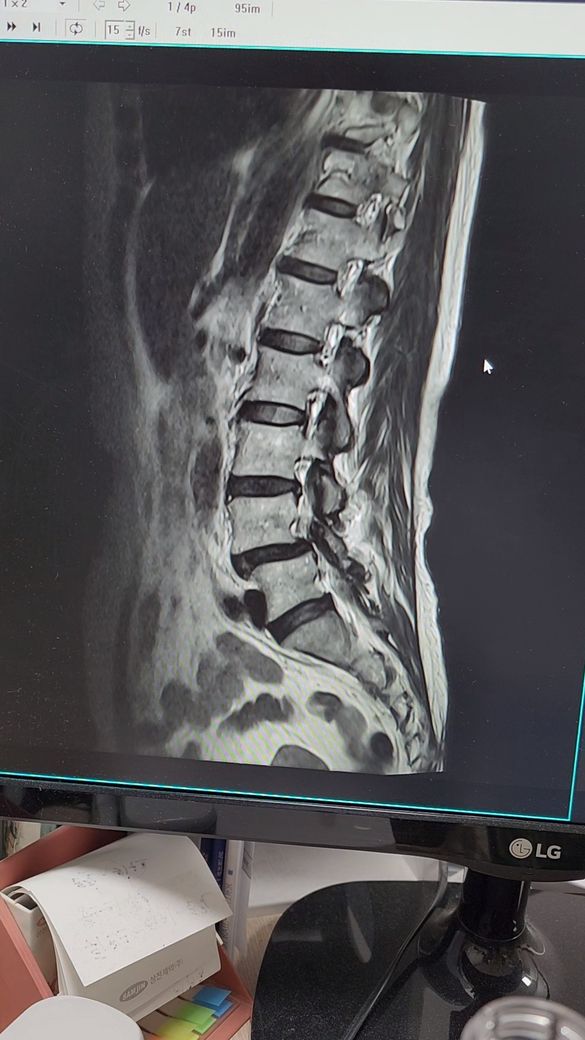

허리디스크 추간판탈출증.전방전위증

4월5일 척추,4.5번

추간판탈출증과 전방전위증으로 왼쪽 엉치부분과 사타구니 허벅지 뒷쪽 방사통과 다리저림이 심해요.처음엔 걷지도 못하고 한달반정도 물리치료,도수치료.약물치료하다가 좋아지질않아서

스테로이드주사4번 맞고 약처방받아서 먹고있는데 통증이 줄었다 심했다 해요. ㅈㅅㄱ교수님동영상보며 걷기도 한시간씩 참아가며 보존치료로 버티고있는데 나날이 통증변덕이심해요. 파행거리가 10분정도.때로는 20분도 괜찮아 지기도하는데 일관성이없어요. 한방 약침치료도 한달해 봤는데 통증이 호전되지않아요. 이럴때 도수치료나 교정치료가 도움이 될까요?